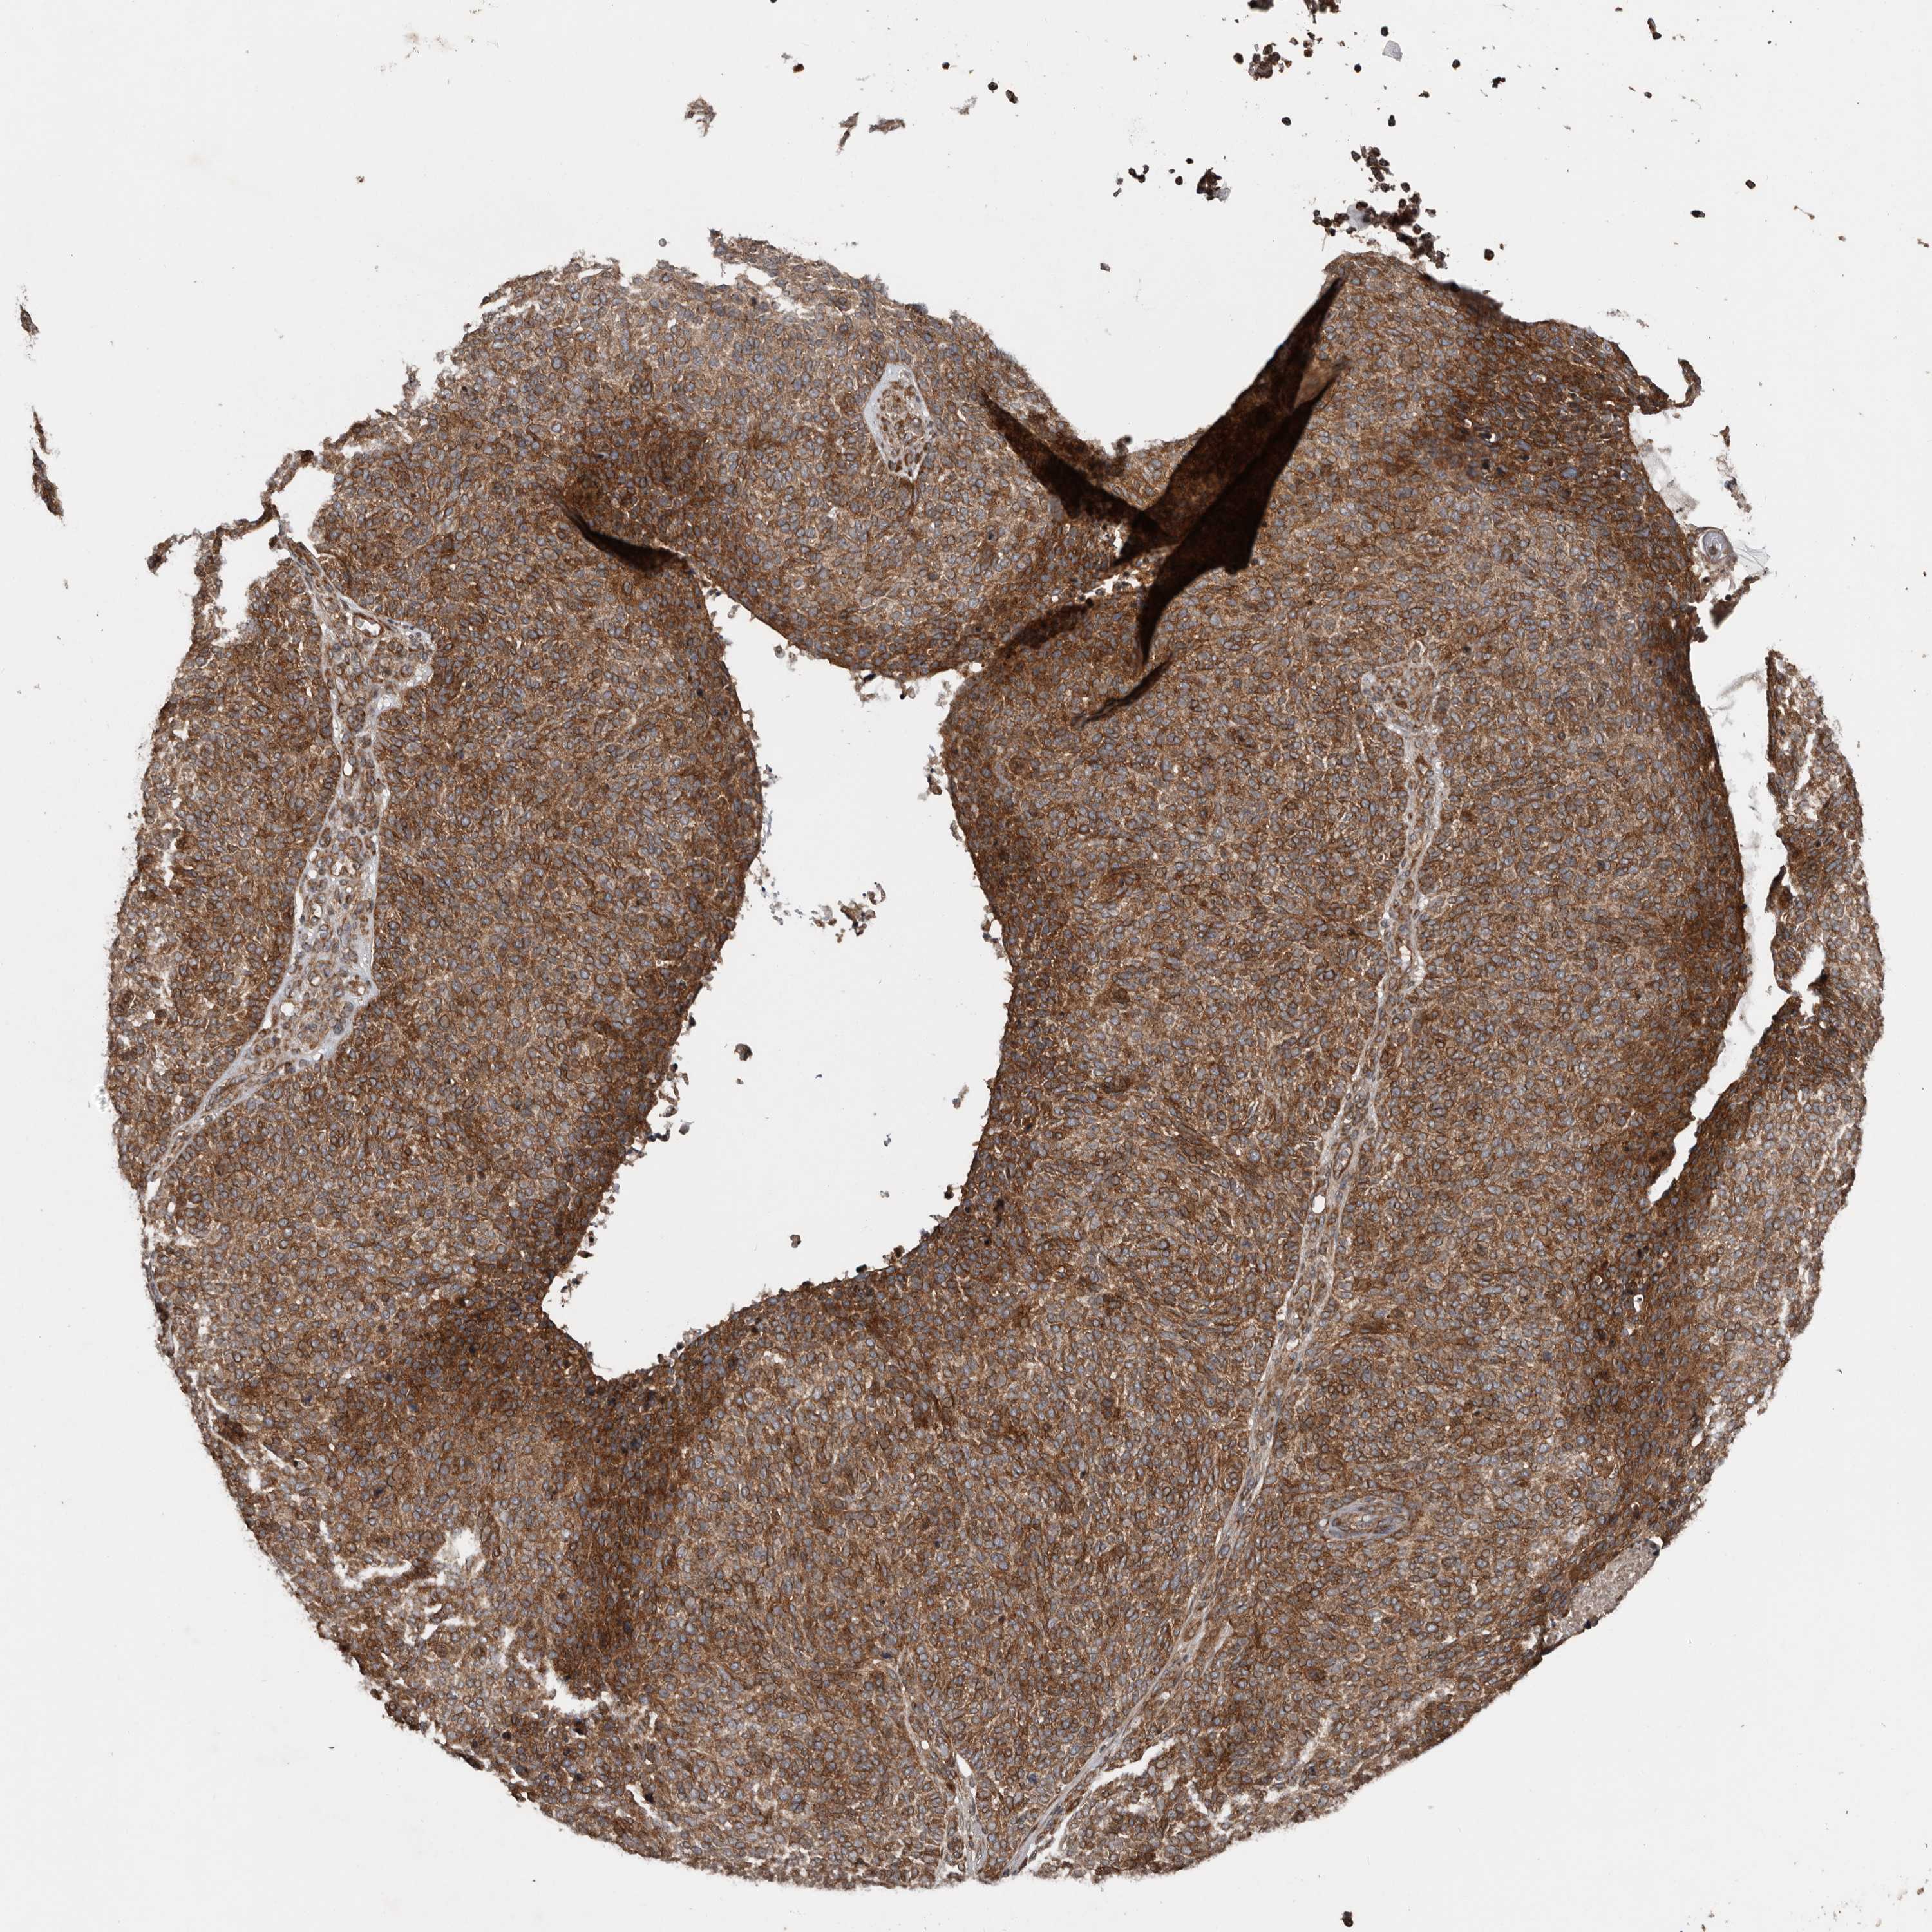

SKIN CANCER - Protein expressioni

A mouse-over function shows sample information and annotation data. Click on an image to view it in a full screen mode. Samples can be filtered based on level of antibody staining by selecting one or several of the following categories: high, medium, low and not detected. The assay and annotation is described here.

Each image is clickable and will lead to virtual microscopy that enables deeper exploration of all samples and also displays staining intensity scores, fraction scores and subcellular localization as well as patient and tissue information for each sample.

Antibody HPA028592

Squamous cell carcinoma, metastatic, NOS